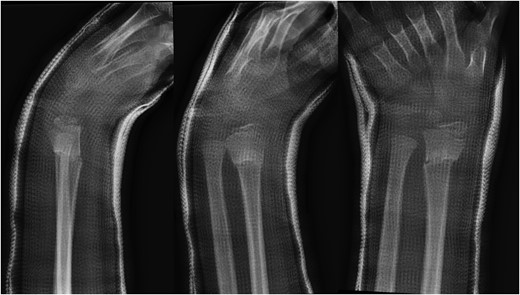

A 10-year-old male was referred to our office after being seen by a pediatric orthopedic surgeon for a distal left forearm mass with block in pronation and supination. The patient's past medical history is significant for a distal radius fracture 2 years prior to his aforementioned office visit. Follow-up radiographs after fracture union at that time showed no evidence of disease (Fig. 1). Radiographs taken at the time of presentation 2 years after fracture healing revealed a 6.5 cm long lesion in the distal syndesmosis arising from the radius. The lesion resulted in pressure erosions upon the distal radius and ulna, causing a slight splaying of the bones (Fig. 2).

Lateral, oblique and anteroposterior (AP) views of distal radius fracture 2 years prior to presentation of desmoplastic fibroma.